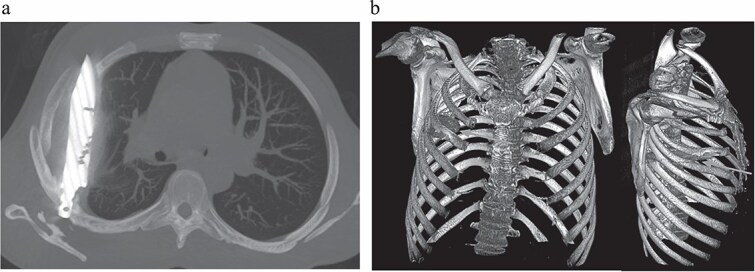

Рентген выявил крупный металлический нож в грудной полости — области, где находятся сердце и легкие. Лезвие длиной от лопатки до передних ребер (между 3-м и 4-м ребрами) было окружено гноем и омертвевшими тканями. КТ подтвердило зажившие переломы лопатки и ребер. Как отметили врачи, организм мужчины создал вокруг ножа фиброзную капсулу, изолировав инородный объект и позволив ему жить с ним годами без симптомов.

Слева: КТ показывает положение ножа. Справа: 3D-реконструкция травмы. (Изображение: Kivuyo et al., CC BY 4.0)